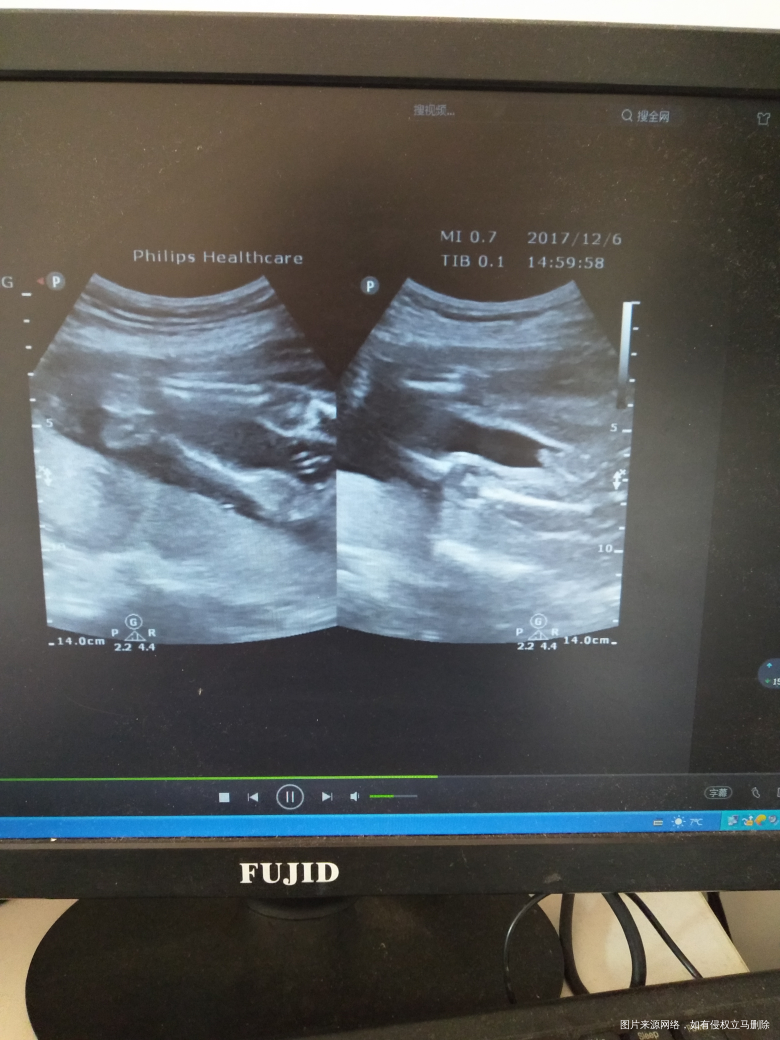

有宝宝的性器官图片 只是我还看不懂?有经验的宝妈可以帮我看一下

吗?

[大笑]下面那张像小鸡鸡

男孩吧

男孩

男宝吧,好清楚

像男孩

小鸡鸡好明显[大笑]